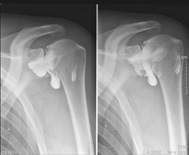

Par exemple, la radiographie |

|

du rachis lombaire en cas de lombalgies |